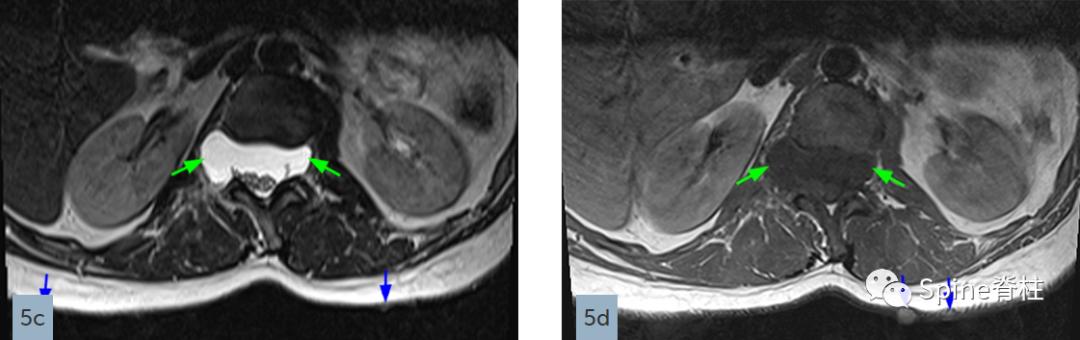

硬膜扩张也是强直性脊柱炎的一种表现,通常累及腰骶部,但不对称骨侵蚀主要累及脊柱后部,包括椎弓根、椎板和棘突。在MRI上,可以发现多发性背侧硬膜憩室(图6),可能与长期强直性脊柱炎有关。

强直性脊柱炎患者L4-5水平的横断面T2(上图)和矢状位T2(下图)加权像提示多发性蛛网膜憩室(arachnoid diverticula)以及椎板和棘突的侵蚀(红色箭头),但需注意憩室周围的神经根粘连